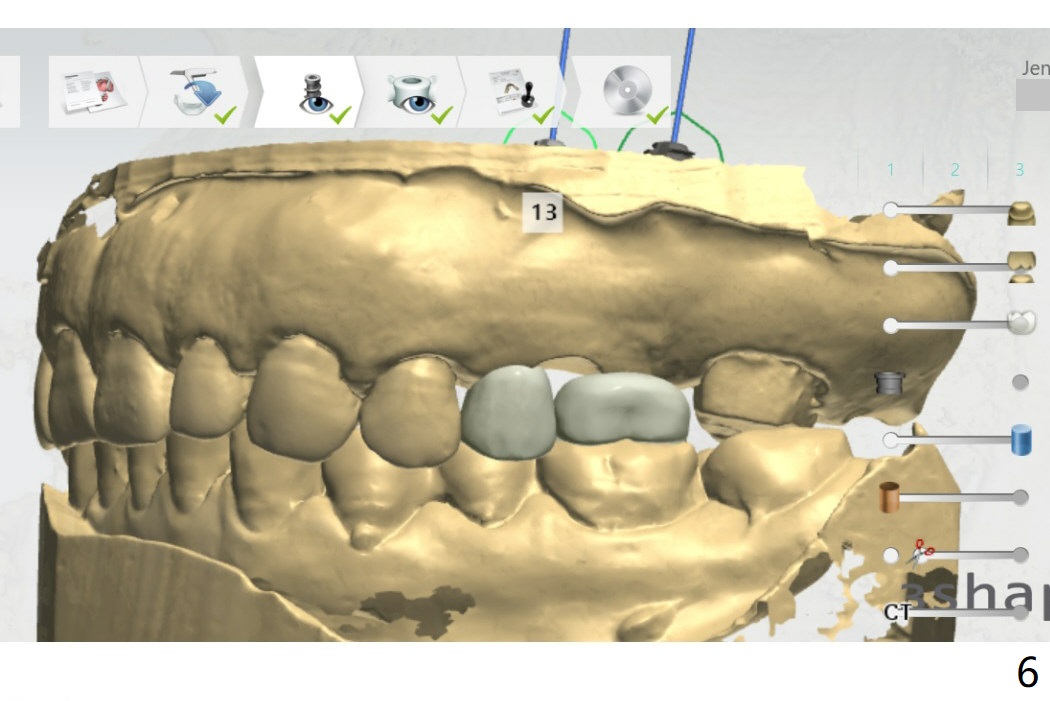

Guide for FPD

Return to Upper Molar Premolar Immediate Implant, Trajectory, Metronidazole